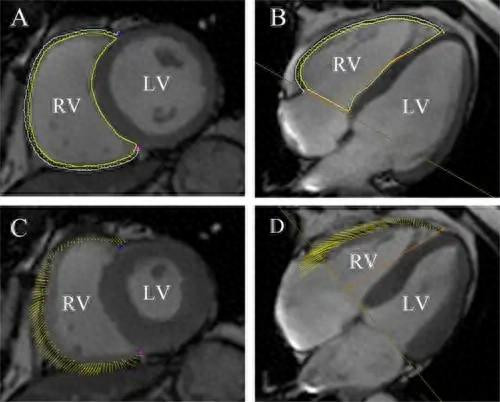

1. 腹黑功能评估

通过电影序列连气儿拍摄腹黑从削弱到舒张的通盘经由,大夫不错精确测量心室容积、心肌质料,并策画出评估腹黑泵血功能的短处主义——射血分数。MRI是现在公认的测量心室容积和射血分数最准确且可重叠性最高的无创查验才智。